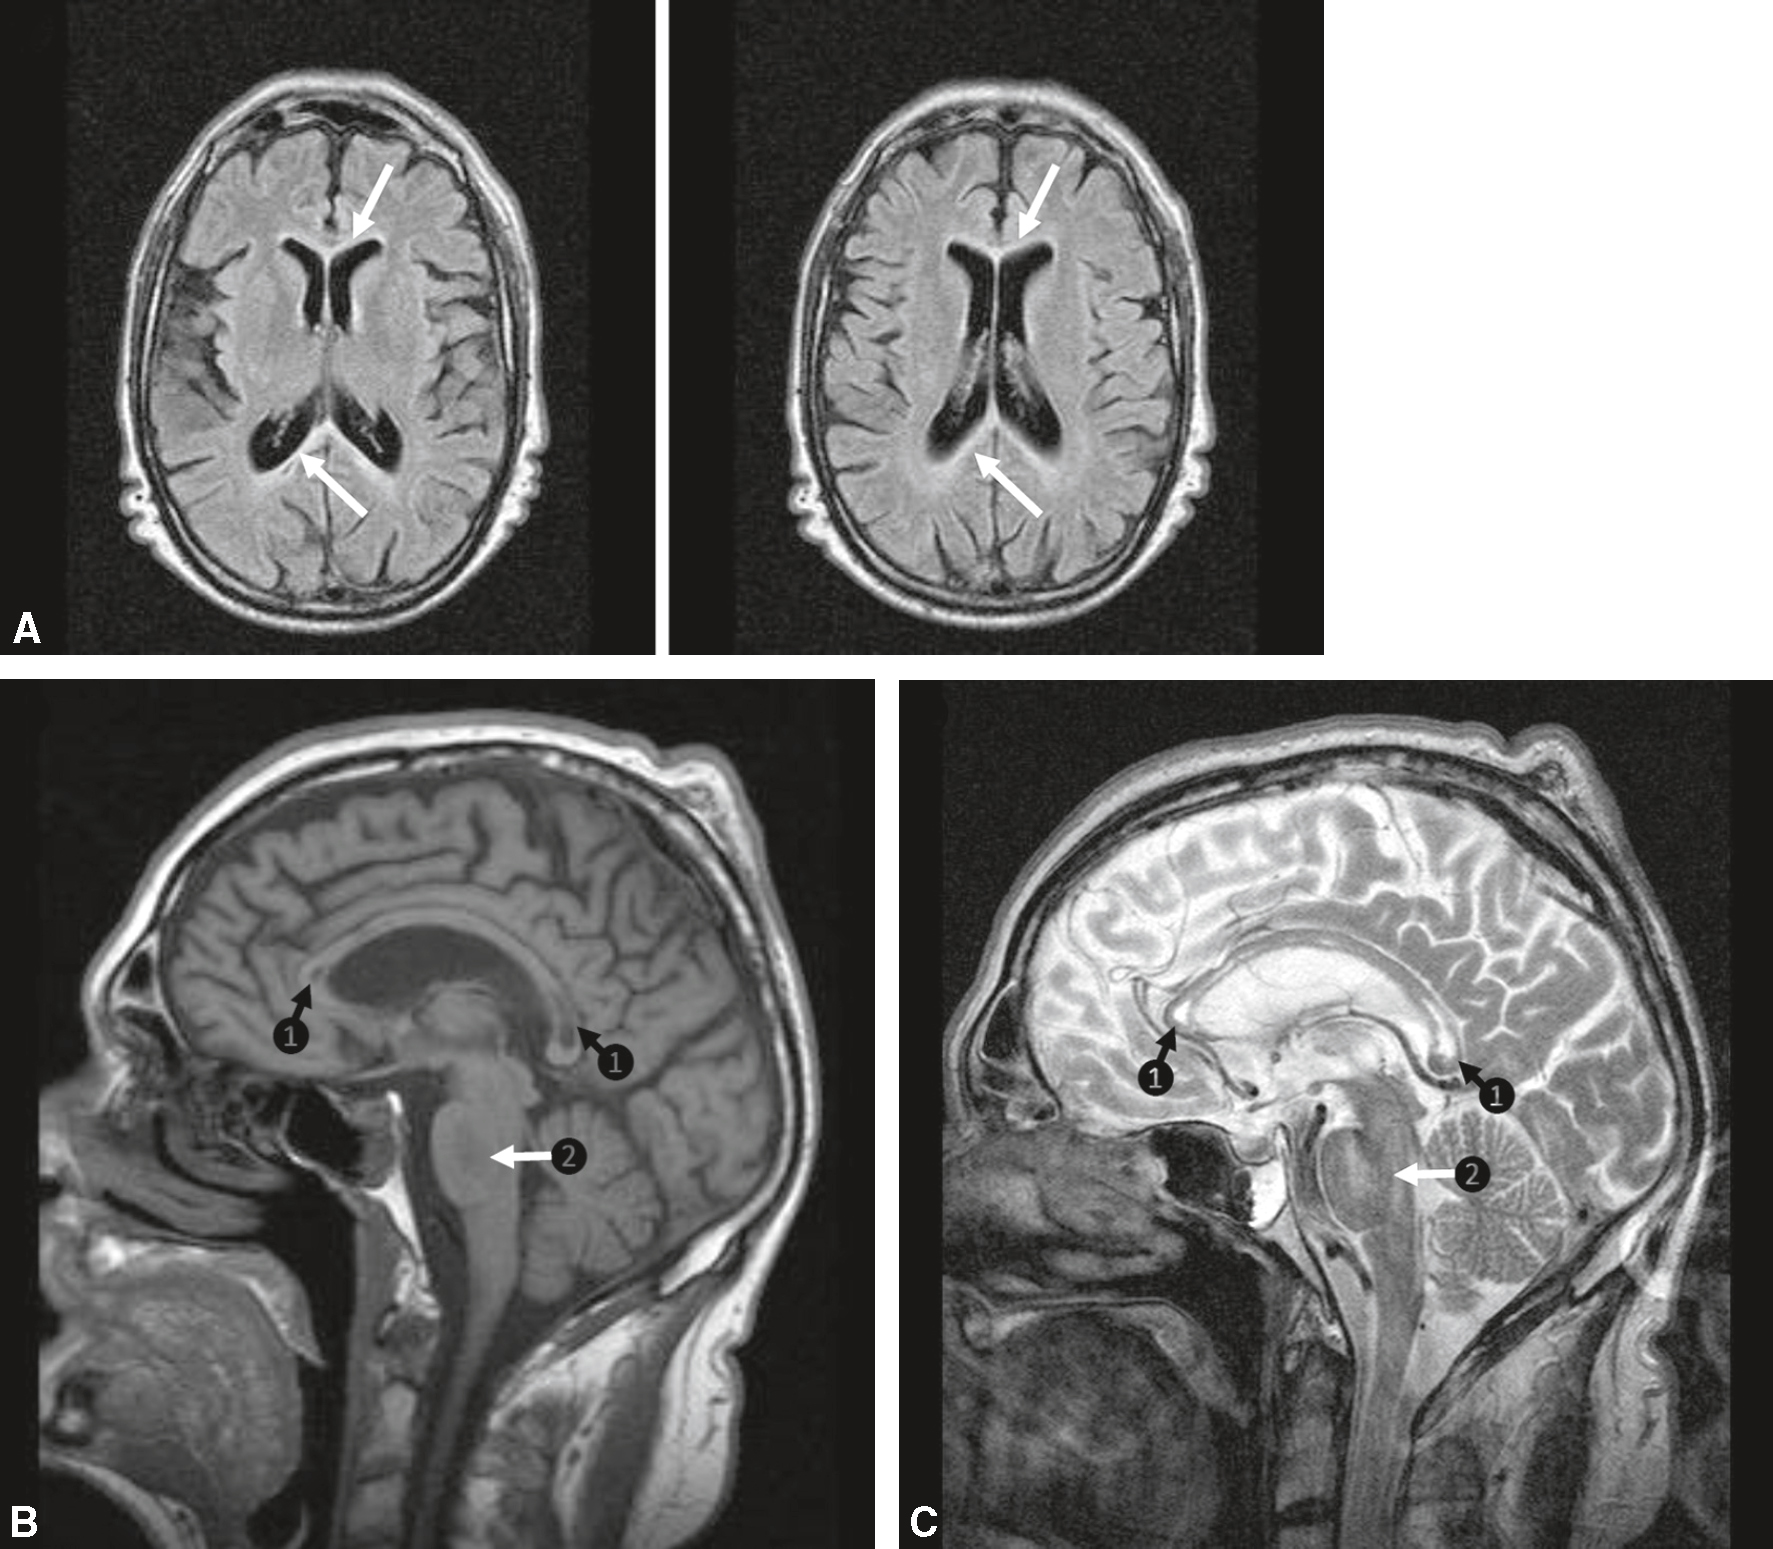

Le diagnostic est confirmé par l’aspect du corps calleux en imagerie : hypodense au scanner (bien visible en avant et en arrière des cavités ventriculaires sur les coupes axiales) et hyposignal T1/hypersignal T2 à l’IRM (fig. 2.2). Le pronostic à moyen terme est classiquement sombre, mais une atteinte limitée avec régression partielle des signes est possible.

Maladie de Marchiafava-Bignami. A. IRM axiale FLAIR. Hypersignaux du corps calleux (flèches blanches). B. IRM sagittale T1. 1. Hyposignaux du corps calleux (flèches noires). 2. Hyposignal du pont (ou protubérance) (flèche blanche). C. IRM sagittale T2. 1. Hypersignaux du corps calleux (flèches noires). 2. Hypersignal du pont (ou protubérance) (flèche blanche).

Sur les coupes axiales FLAIR (A), on observe un hypersignal symétrique du corps calleux, plus marqué en région moyenne et postérieure, avec des flèches blanches pointant ces lésions. En sagittal T1 (B), la flèche blanche marquée 2 montre une zone d’hyposignal localisée dans la partie moyenne du corps calleux (corpus callosum), traduisant une démyélinisation. Les flèches noires numérotées 1 désignent l’atteinte du splénium et du genu, parties postérieure et antérieure du corps calleux respectivement. En C, coupe sagittale T2, on retrouve les mêmes localisations avec un hypersignal du corps calleux (repères 1) et du pont (repère 2), caractéristique d’une démyélinisation alcoolique. Aucun effet de masse ni rehaussement n’est observé, ce qui appuie le diagnostic de maladie de Marchiafava-Bignami.